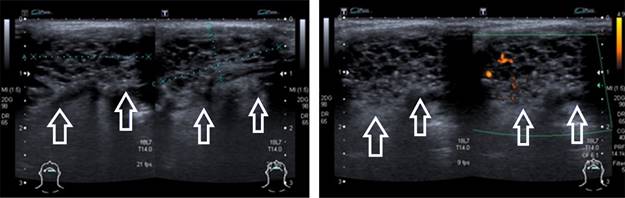

Se indicó un nuevo ultrasonido en el que se localizó una lesión en línea media cervical, sublingual, de morfología ovalada, de bordes bien definidos, con medidas de 21 × 9 × 22 mm, el volumen aproximado de 2.2 cm3; heterogénea a expensas de múltiples imágenes hipoecogénicas redondeadas, de bordes bien definidos. A la aplicación de Doppler color se presentó flujo intralesional, concluyendo: tiroides ectópica sublingual, con presencia de múltiples quistes coloides (Figura 1).

Figura 1: Ultrasonido Doppler color que muestra presencia tiroides ectópica de situación sublingual, múltiples imágenes hipoecogénicas redondeadas, Doppler color con flujo intralesional.